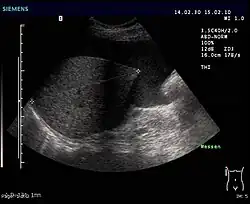

- Sonografie (Ultraschall): Geringe Mengen von Aszites lassen sich dabei am ehesten am Unterrand der Leber oder knapp oberhalb der Harnblase nachweisen. Der Raum zwischen Leber und Niere (Morison-Grube oder Recessus hepatorenalis) ist im Liegen der tiefste Punkt des Oberbauchs.